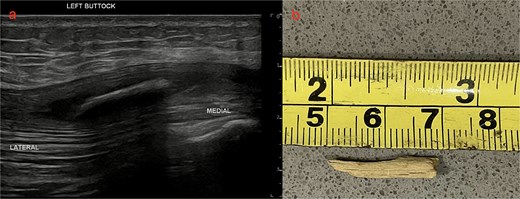

A targeted US was performed, showing a 20 × 2 mm FB buried within the left gluteus maximus, 12 mm deep. On surgical re-exploration, the gluteus muscle was opened over the US guided markings. A sinus tract was identified which communicated with the previously identified lumbosacral tract. A strip of gauze was threaded through the tract and flossed to remove a fragment of wood (Fig. 3).

US left buttock and photo of wooden splinter (a) US left buttock shows a 20 × 2 mm hyperdense foreign body within the left gluteus maximus 12 mm deep. (b) Photo of wooden splinter after retrieval.